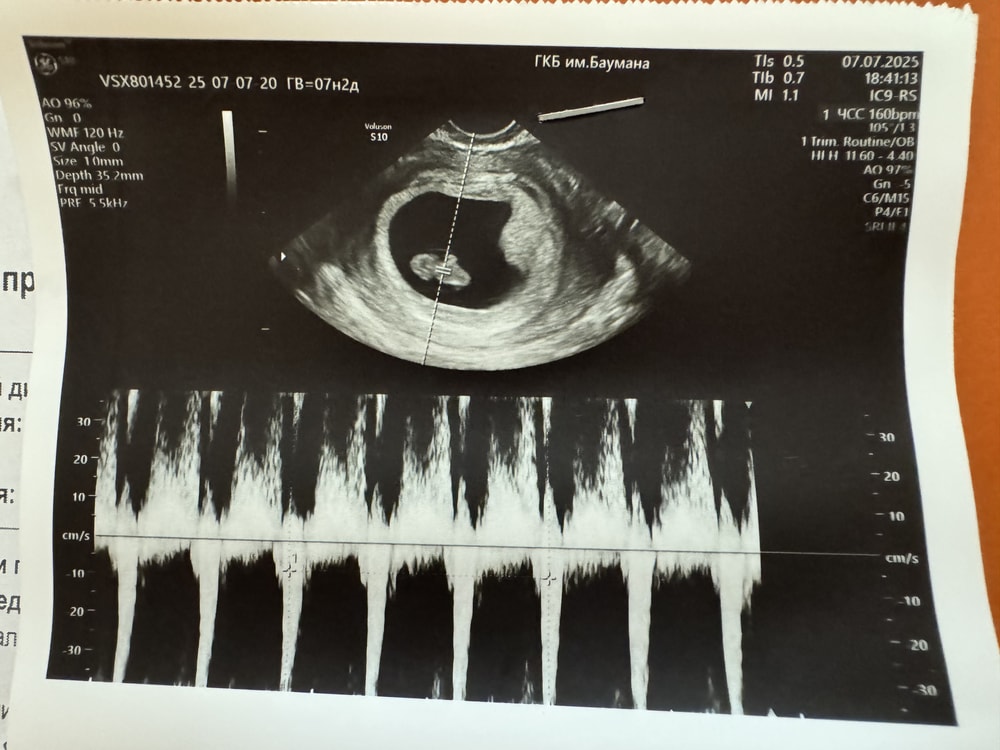

УЗИ 7-8 недель

А так растем хорошо, чему я очень рада)) По месячным вчера срок был 7н2д, по овуляции 7н5д, а по узи поставили 8н0д. Сказали, что к 1му скринингу срок станет точно понятен.

КТР 1,57 см

ЧСС 160 уд/мин